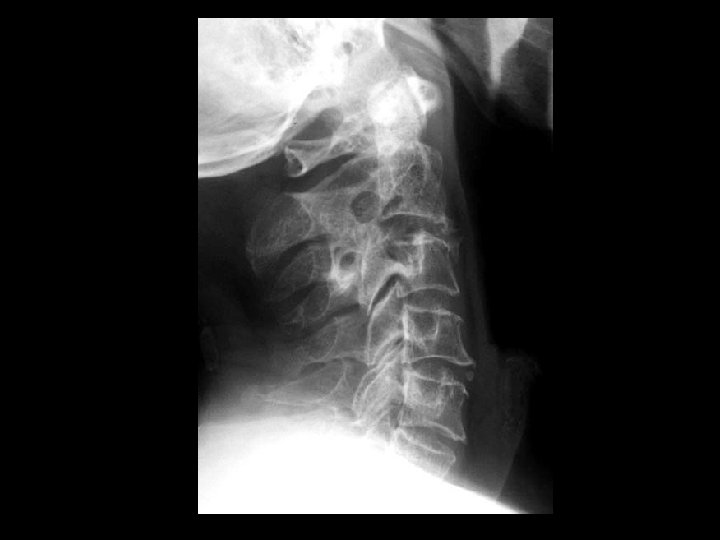

Rheumatoid arthritis • Findings: – Destruction of the dens and the anterior C 1 arch by a soft tissue mass – Impression of the anterior thecal sac with slight deformation of the cervical cord • ddx: – Infection – Metastasis